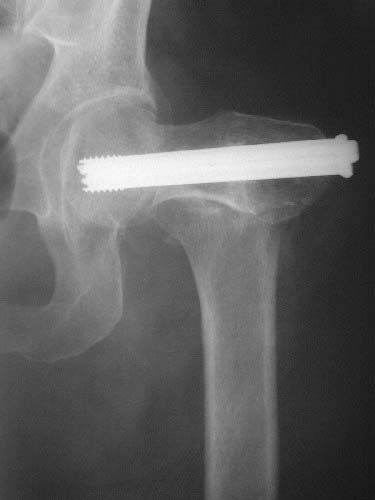

Does anyone on the list know of any references regarding the placement of cannulated hip screws above/below the lesser trochanter as it relates to the risk of subsequent subtroch fracture? i know placement should be above the lesser trochanter but i have been unable to find evidence to support this. thank you.

Reported 20% incidence of fracture if screws are placed too low, below the lesser trochanter, or  with un-filled drill holes there too. I have not looked at it in a long time but I believe the reference on this topic is: Karr, Clin Ortho Rel Res 1985.